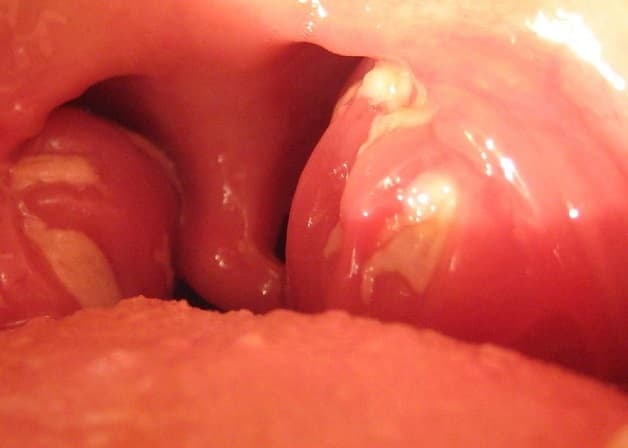

Hình ảnh áp xe quanh amidan

Viêm quanh amidan tiến triển rất nhanh. Khi thăm khám sẽ thấy amidan bị sưng rất to, đỏ và phủ mủ trắng trên bề mặt xong rất dễ loại bỏ mủ này. Mặt trước amidan có dấu hiệu bị căng phồng, biểu hiện phù nề. Quan sát lưỡi gà phù mọng nước và kém di động. Ổ áp xe thường xuất hiện quanh 1 bên amidan kéo theo hạch sưng to, chạm nhẹ có cảm giác đau. Thực hiện các xét nghiệm và phân tích phát hiện thấy các tế bào bạch hầu trung tính tăng.